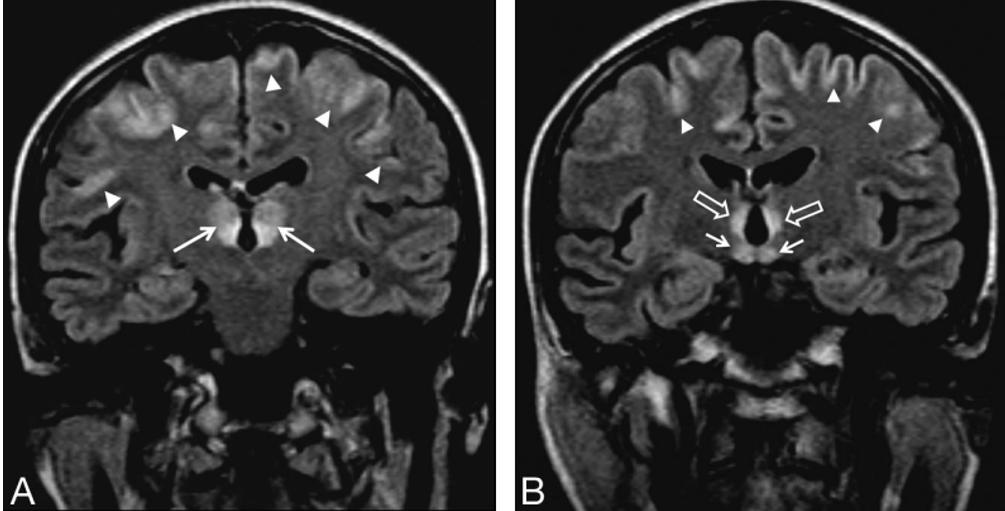

男,54歲,絕食后意識障礙。Flair示雙側丘腦、額葉皮層、乳頭體和第三腦室周高信號。

病例7

患者表現(xiàn)為意識障礙、肢體不自主運動、小腦性共濟失調、眼球震顫、雙側外直肌麻痹。顱腦MRI示:雙側小腦齒狀核(空箭頭)、前庭神經(jīng)核(白色箭頭)、展神經(jīng)核異常信號(短箭頭);中腦頂蓋、雙側黑質及乳頭體對稱性異常信號。